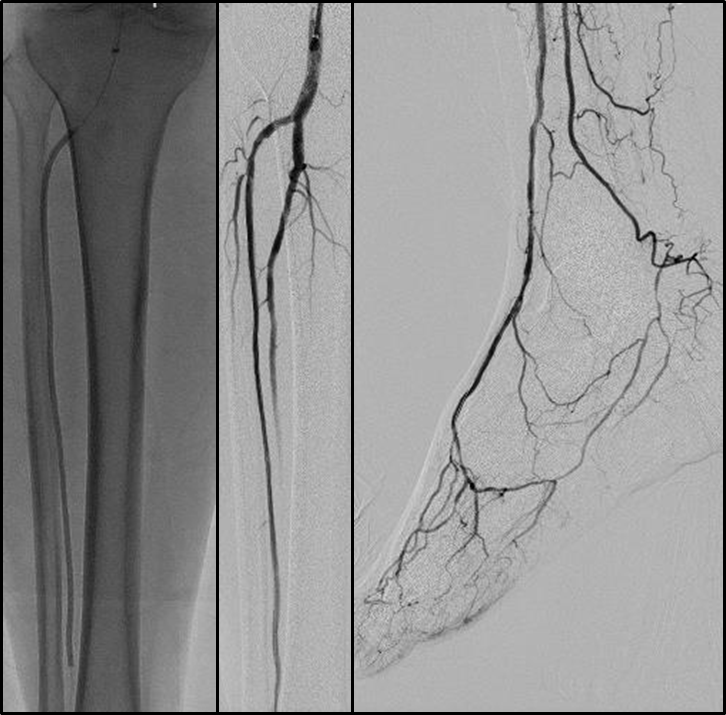

BTK病变多为长段、弥漫、钙化、CTO,多累及踝下(BTA)

病变常为单个或多个CTO组合,总长度可达20cm;

部分患者存在踝上交通动脉或完整的踝下足底弓,为逆向开通提供可能。

通过深入剖析解剖规律、明确技术选择边界、并提出一套简化的标准化流程,为临床医生处理BTK-CTO病变提供了清晰、实用的操作指南,有助于提高手术成功率,改善CLTI患者的保肢预后。